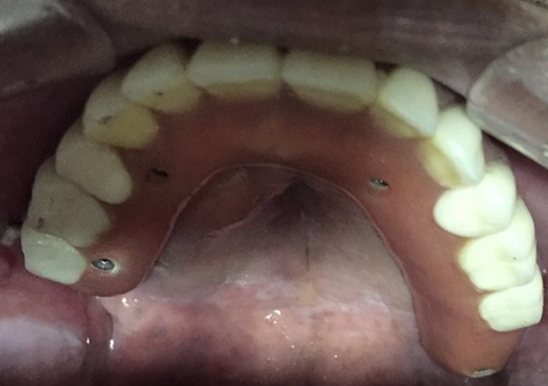

Paciente de 54 anos, do sexo masculino, apresentando boa saúde geral, relatou que procurou atendimento odontológico para realizar a manutenção regular de sua prótese maxilar implanto-suportada do tipo protocolo, instalada há oito anos. O profissional que o atendeu não solicitou nenhum tipo de exame radiográfico e, ao tentar remover a prótese do paciente, não conseguiu remover os parafusos de fixação. Nesse processo, notou a presença de secreção purulenta, então utilizou o fórceps para remoção forçada da prótese, o que terminou por fragmentar dois implantes do paciente de difícil remoção, e fraturar um parafuso de fixação. Um dos implantes foi avulsionado (Figura 1). Perante essa situação, o profissional o informou que seus implantes eram irreparáveis.

O paciente então, procurou o consultório para uma nova avaliação. Foi realizado exame clínico inicial e análise de exames radiográficos (Raio X panorâmico e tomografia computadorizada). Durante a avaliação clínica, houve extravasamento de secreção purulenta de cor amarelo citrino, e, através dos exames radiográficos pode-se constatar que um dos implantes havia rompido a parede do seio maxilar, e ali se instalado, desencadeando a infecção (Figura 2). Através dos exames radiográficos constatou-se também ausência de quantidade óssea suficiente para reabilitação do paciente por meio de novos implantes convencionais, exclusivamente (Figura 3). Além disso, verificou-se que o paciente possuía periodontite nos dentes remanescentes da mandíbula, com mobilidade de grau 3.